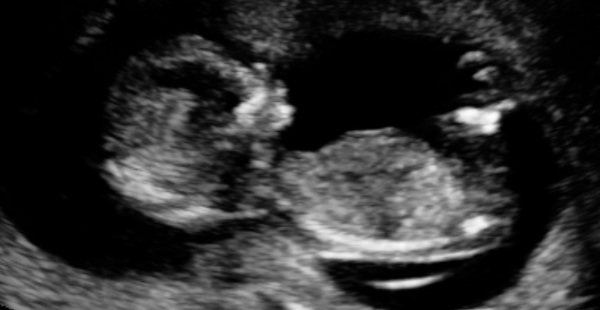

Second attempt at 12 week nuchal scan a success woohoo. Ghost or anyone want to try out the skull theory? Sonographer said 'don't paint your nursery yet but I think it's a...'

Dream... I'm saying girl...

dream based on skull theory - boy!